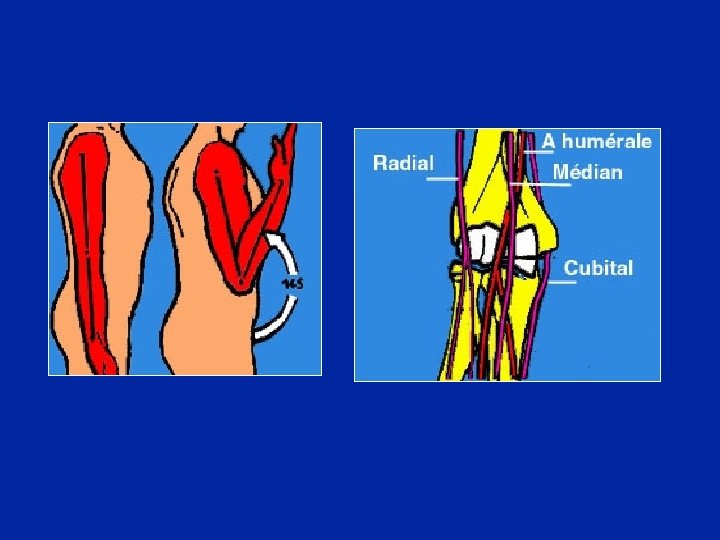

Relaciones del nervio cubital